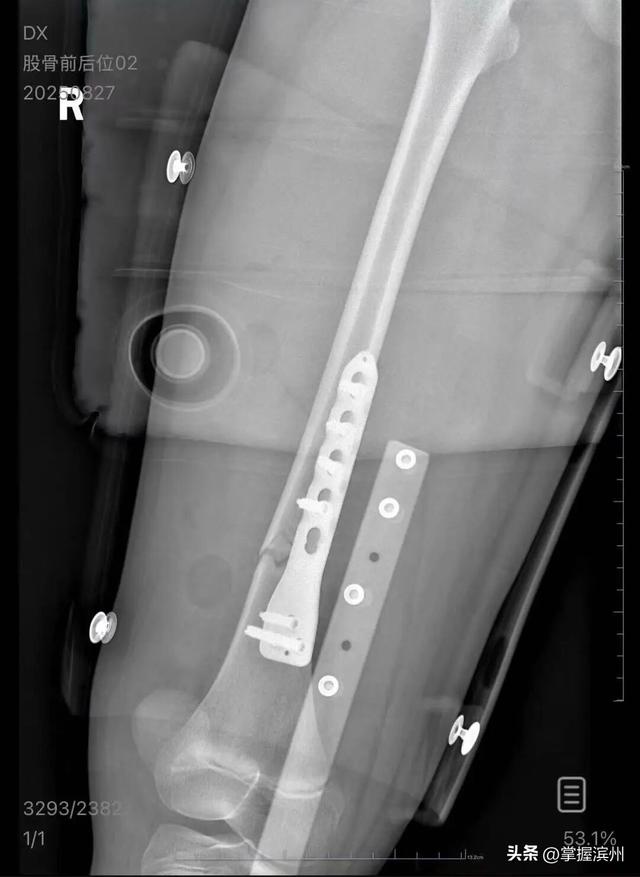

▲朱女士女儿手术后拍的X光片 受访者供图

朱女士向记者出示的医院病历显示,8月24日凌晨,朱女士的女儿到医院就诊。医院诊断朱女士的女儿右股骨骨折,需要住院进一步治疗。

朱女士告诉扬子晚报/紫牛新闻记者,医疗费加上护工费已经花费了5万多元,“而且在出院以后,医生说因为植入了钢板,后续孩子可能会有后遗症,最有可能出现的是长短腿,让我们去做康复治疗,这就面临着另一笔费用。”